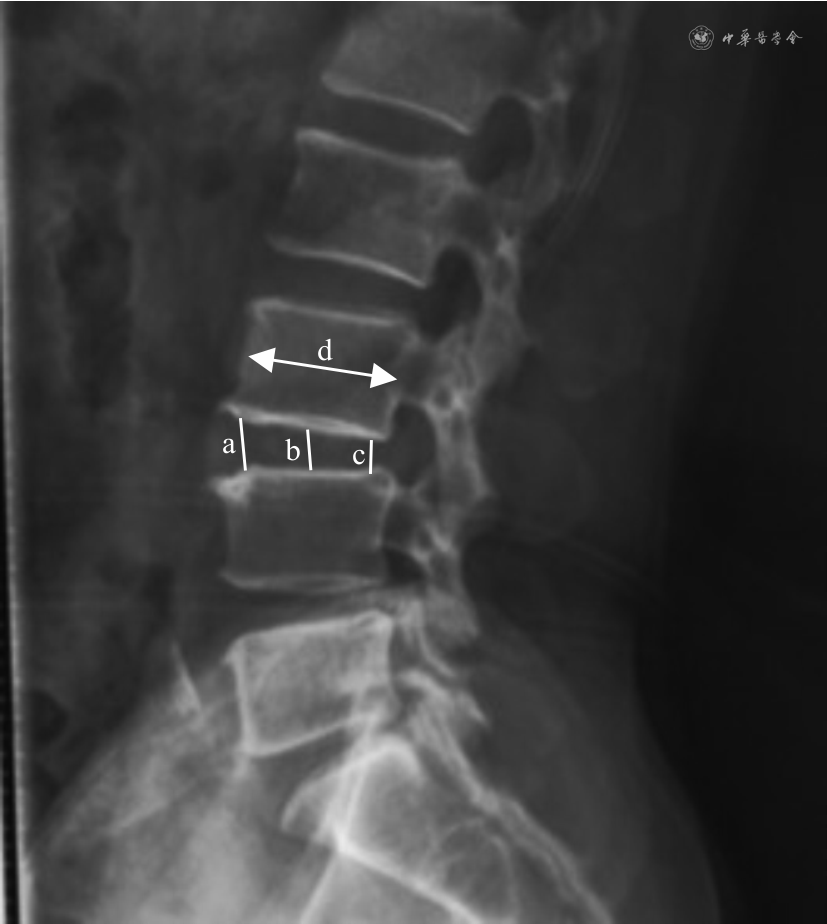

(1)2组患者基线资料,手术时间、切口长度、出血量等围术期指标,以及硬脊膜撕裂、神经根损伤、血管损伤、椎间隙感染等手术并发症。(2)采用改良ODI 评估2组患者在术前及术后1、3、6个月的神经功能情况。(3)采用VAS 评分评估2组患者术前及术后1、3、6个月腿痛情况。(4)采用椎间盘高度指数(disc height index,DHI)评估患者手术前后椎间高度变化,进而间接评估脊柱稳定性:术后DHI增加意味着脊柱不稳定及腰椎间盘突出术后复发风险增加[9]。DHI测量计算方法示意见图1。

注:a 为椎间盘前缘高度;b 为椎间盘中线高度;c 为椎间盘后缘高度;d 为上位椎体矢状径

DHI=[(椎间盘前缘高度+椎间盘中线高度+椎间盘后缘高度)/3]/上位椎体矢状径